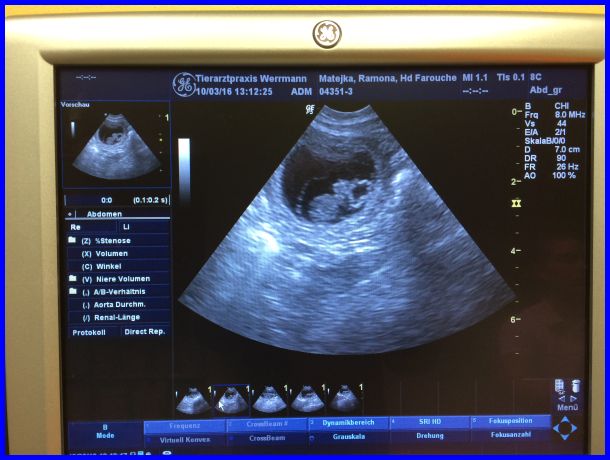

Im oberen Teil des Bildes ist die Fruchtblase als schwarzer Kreis zu erkennen, das graue Gebilde darin ist ein Welpe.